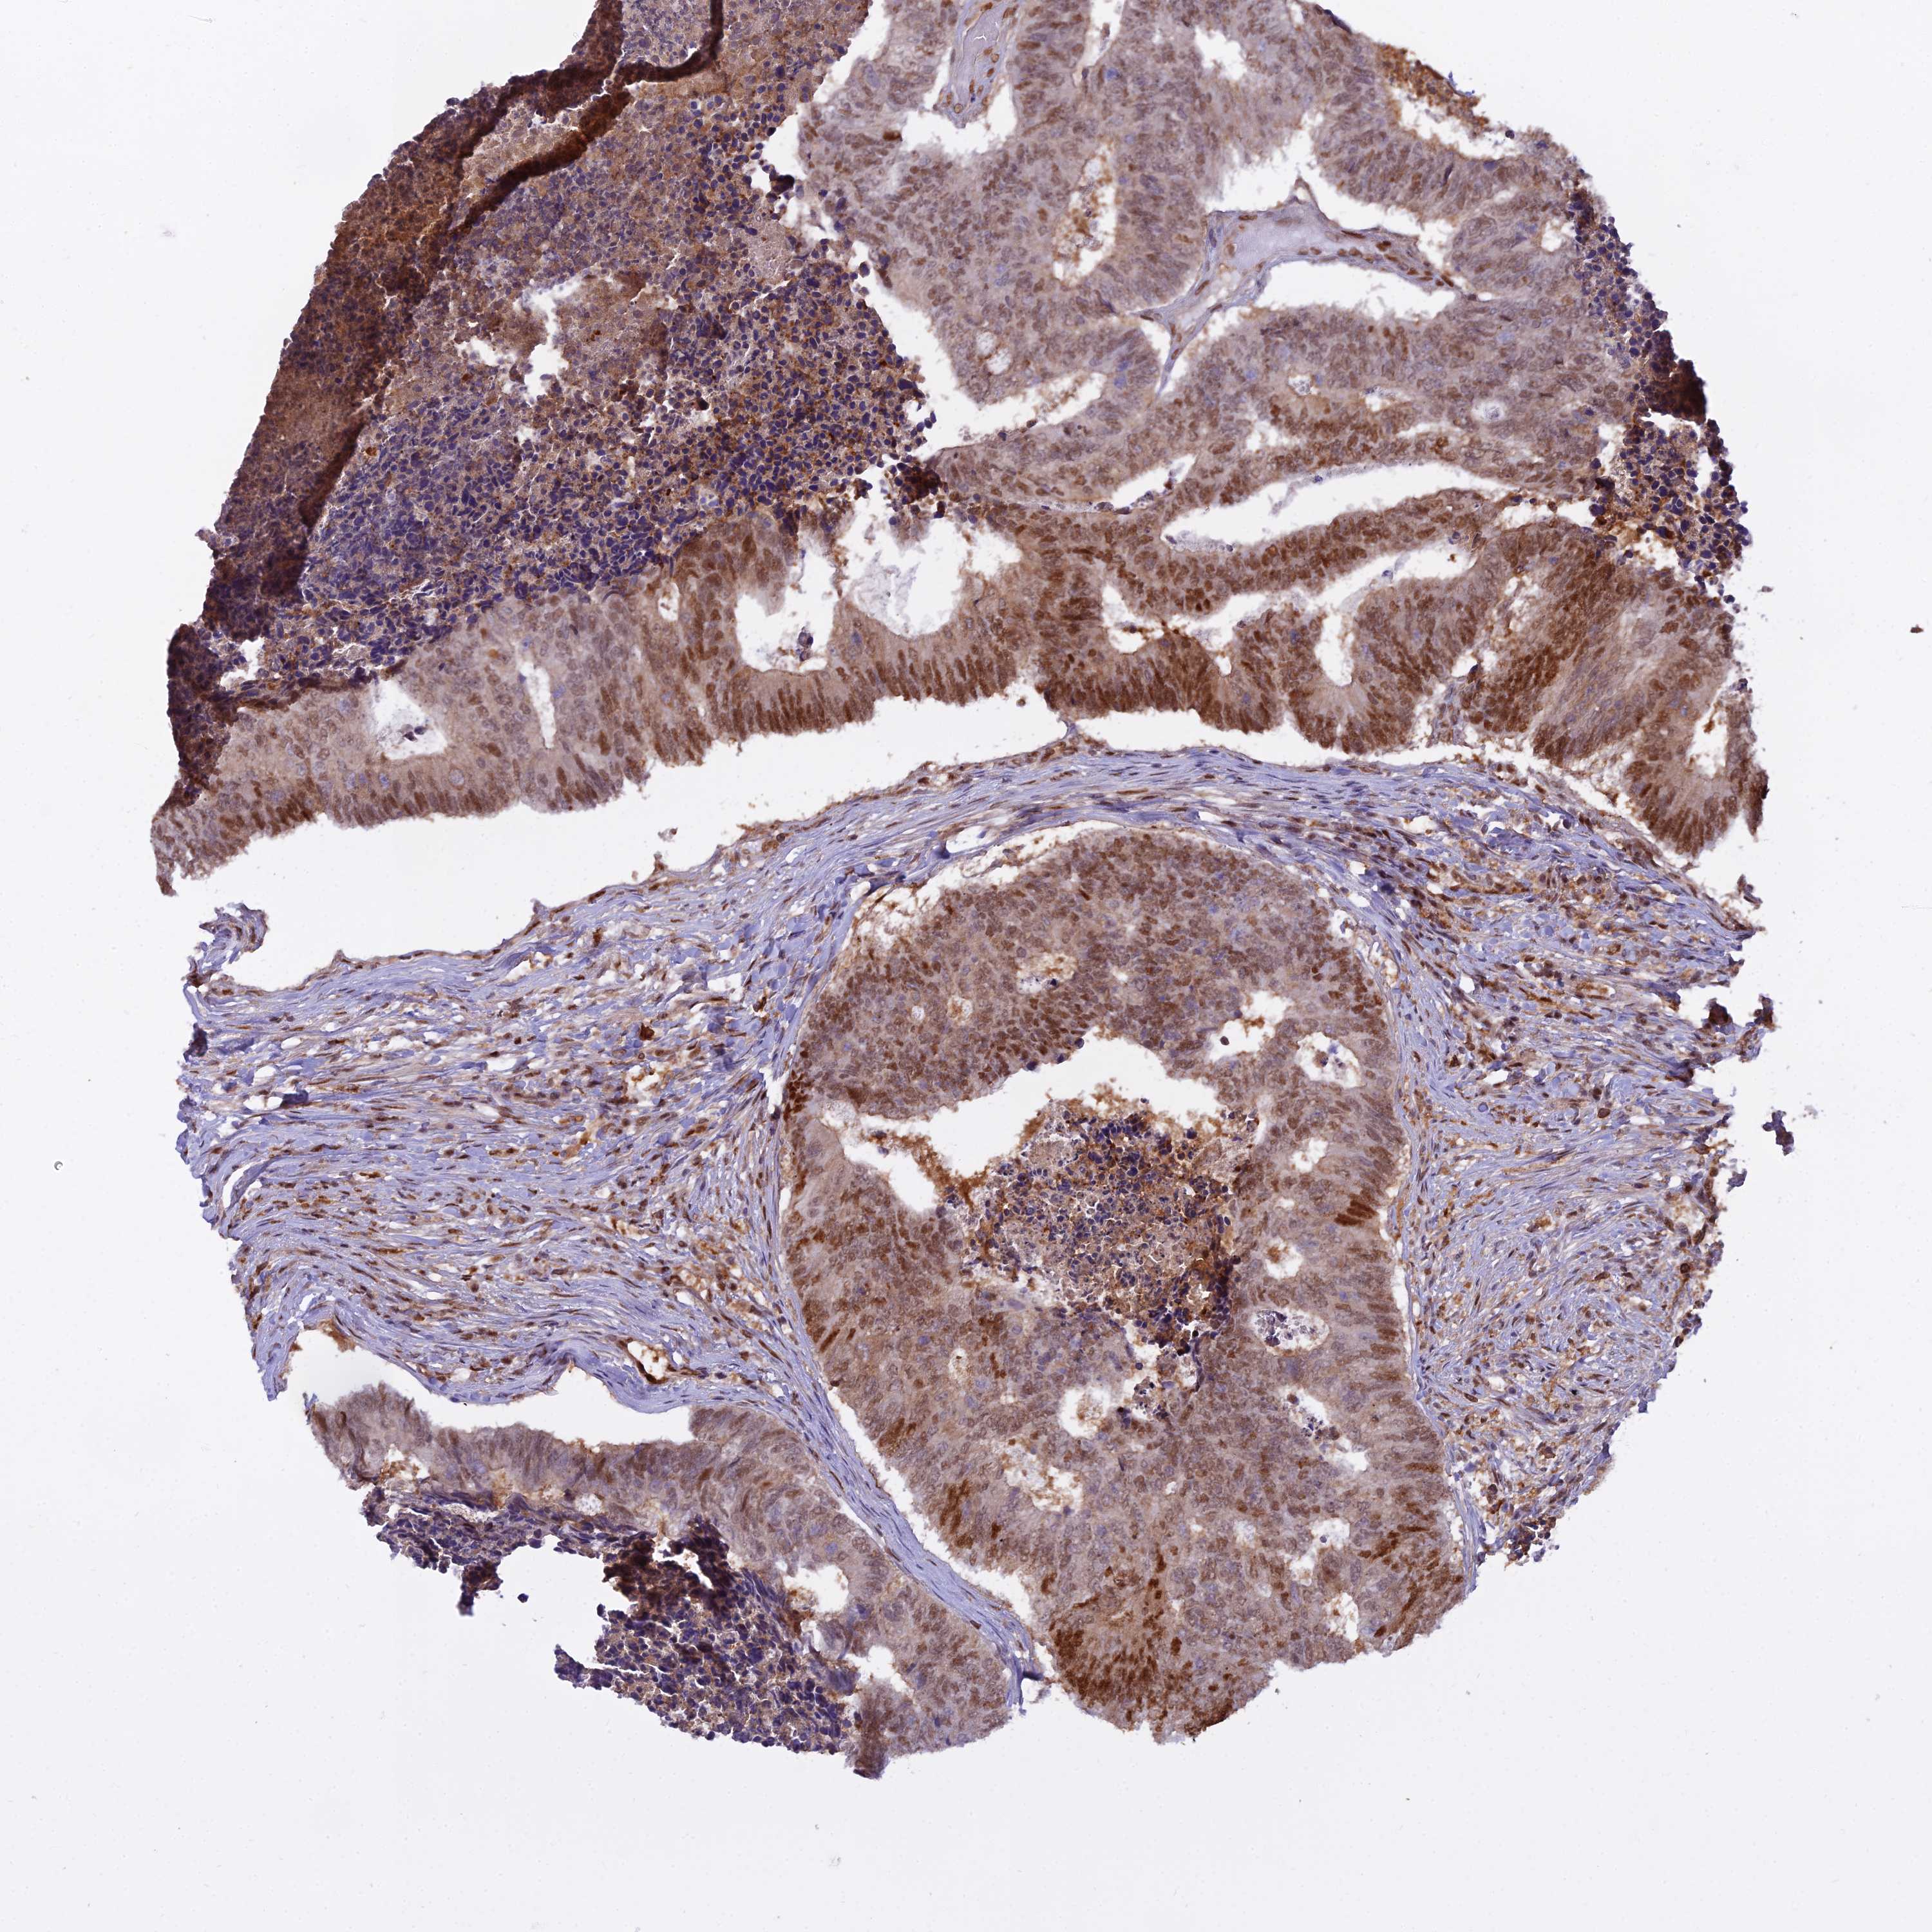

ANTIBODIES

AND

VALIDATION

Colorectal cancer

Human cancer

Colon adenocarcinoma

Rectum adenocarcinoma